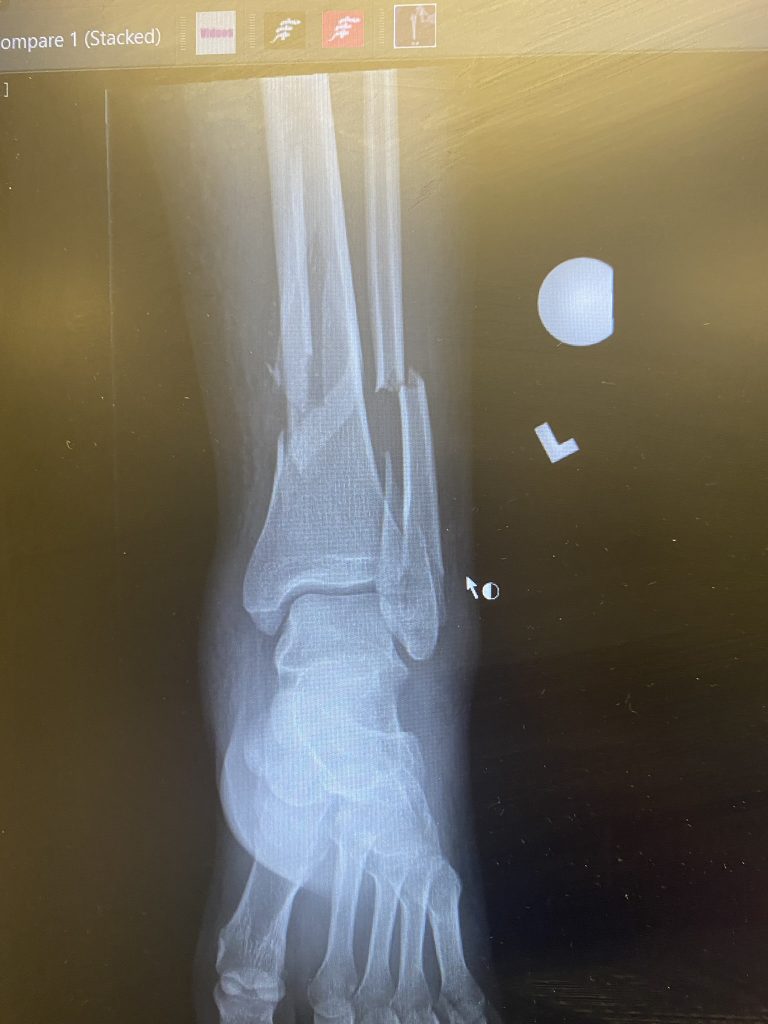

In January 2022, I tripped on an uneven sidewalk causing a closed fracture of my left tibia and fibula and Type I or II open fracture of left tibia and fibula. I did not realize the affect this injury would have on my family and I. I went to the hospital and they immediately told me I needed surgery as soon as possible. Right after my first surgery I was told they were only able to operate on my tibia due to severe swelling on my fibula. After the surgery I was not allowed to bear any weight and used crutches to get around. I also had a wound vac that connected to my leg that helped with the healing. About two weeks later I received my second operation on the fibula. I remained non-weight-bearing for about 3 months. Within the months after the second surgery I was put into a boot instead of a splint cast which was much more comfortable since you can take it on and off. Then I was able to start physical therapy and focus on getting back to my daily activities. I later received two more operations to remove some of the hardware that was put in during my first two surgeries.